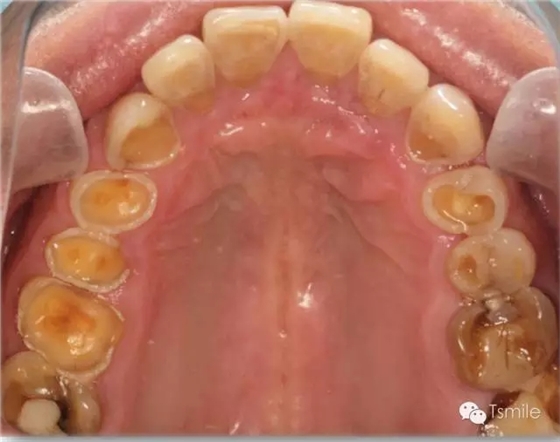

圖1: 夜磨牙導(dǎo)致的牙列重度磨耗

磨耗患者中還有一類(lèi)特殊的局限于上下前牙區(qū)的牙齒重度磨耗,表現(xiàn)為上前牙舌面、下前牙切端和唇面的重度磨耗。該類(lèi)患者常表現(xiàn)為一類(lèi)特殊的咬合類(lèi)型,重度深覆頜或者上前牙明顯舌傾,這種咬合類(lèi)型導(dǎo)致下頜前伸功能運(yùn)動(dòng)受限,從而導(dǎo)致前牙區(qū)重度的磨耗,可稱(chēng)為前牙功能范圍受限(restricted envelope of function)。